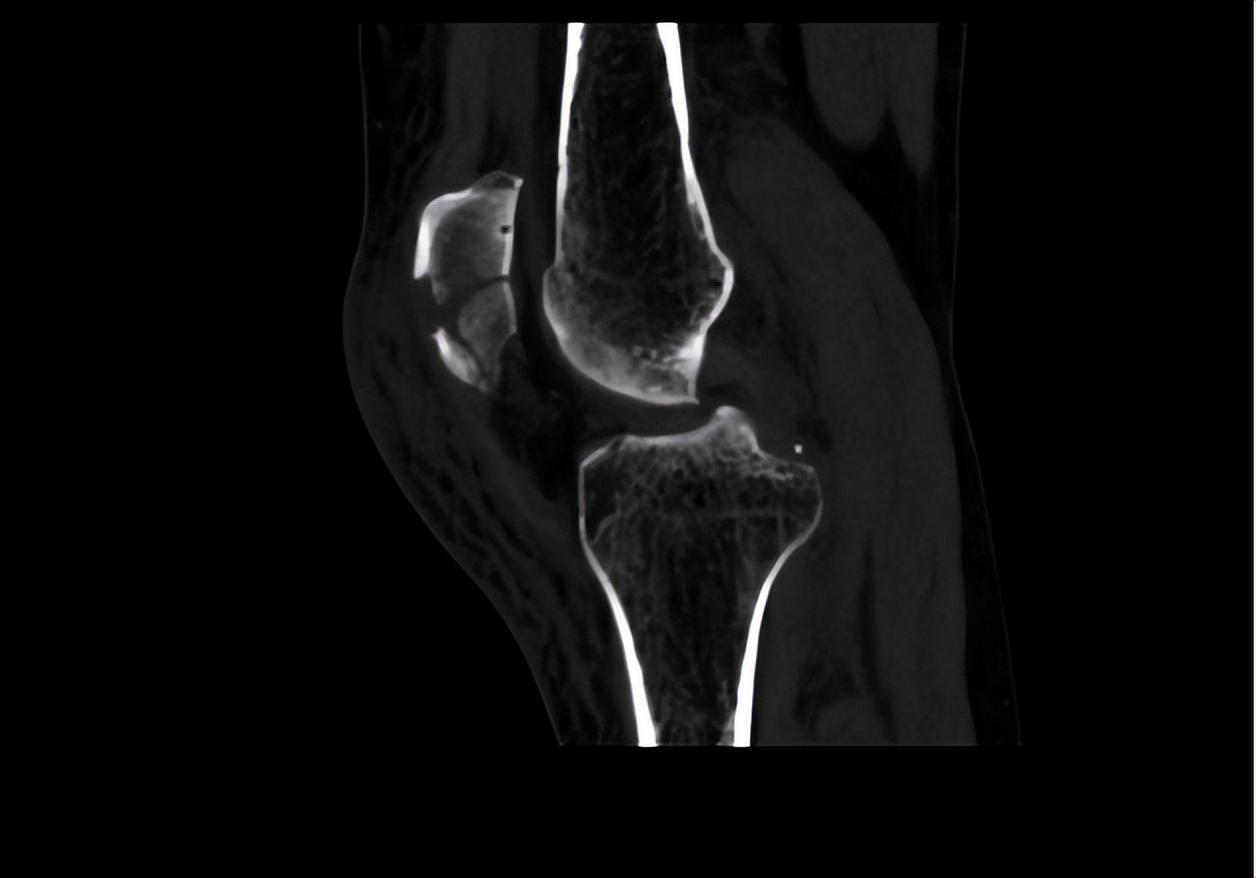

二、調(diào)節(jié)過(guò)程針對(duì)患者目前左髕骨骨折的情況,首要調(diào)節(jié)為進(jìn)行手術(shù)調(diào)節(jié),所以待患者入院后,我立刻給她開(kāi)了相關(guān)檢查,以排除手術(shù)禁忌。完善血常規(guī)、肝腎功、電解質(zhì)、大小便常規(guī)、凝血功能、輸血前檢查等均未見(jiàn)異常。同時(shí)我也讓患者完善了心電圖、彩超、CT檢查和X影像學(xué)檢查。雙下肢彩超提示:雙下肢動(dòng)脈輕度輕度粥樣硬化。左膝關(guān)節(jié)平掃CT+二維、三維重建顯示:髕骨骨折,少量關(guān)節(jié)積液。心電圖未見(jiàn)異常。

綜合患者癥狀、體征及輔助檢查,目前可以明確診斷為“左髕骨骨折”,完善相關(guān)檢查未見(jiàn)手術(shù)禁忌,因此我決定為患者行“髕骨骨折切開(kāi)復(fù)位張力帶鋼絲內(nèi)固定術(shù)”。手術(shù)調(diào)節(jié)能給予較牢固的內(nèi)固定,讓患者早期活動(dòng)膝關(guān)節(jié),防止創(chuàng)傷性關(guān)節(jié)炎的發(fā)生。所以在患者入院后第3天,在腰麻下為患者行“髕骨骨折切開(kāi)復(fù)位張力帶鋼絲內(nèi)固定術(shù)”。手術(shù)順利,術(shù)后患者安返病房,術(shù)后予以消炎、加強(qiáng)換藥、補(bǔ)液、對(duì)癥支持等調(diào)節(jié)。